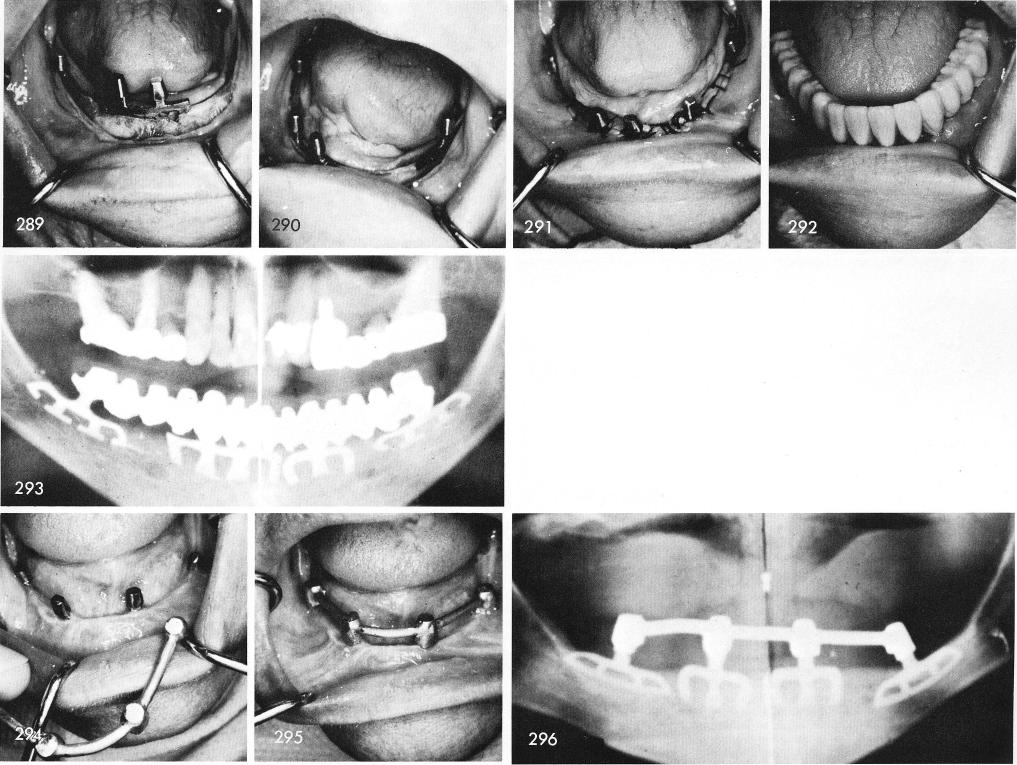

285 and 286 reveal the extremely thin ridge. A clean and steady groove is first made posteriorly, fig. 287, and carefully the blade is gently tapped into proper position, fig. 288. The ridge is widened anteriorly so that blades can also be successfully inserted there, figs. 289, 290. The remaining blades are inserted and the tissues are sutured, fig. 291, and the prosthesis cemented into position, fig. 292. A nine year post-operative x-ray reveals this successfully functioning case, fig. 293.

In those situations where the patient cannot afford a full arch fixed restoration then a Dolder bar-coping support should always be constructed and cemented over the blade posts, figs. 294, 295, which in turn will serve as a support for the removable denture. The post-operative x-ray fig. 296.

1 Widening mandibular ridge anteriorly for inserting blade implants